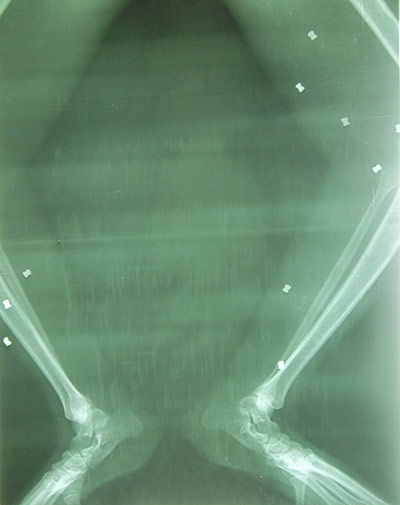

X-rays showed 104 pellets scattered all over her body, including vital organs, her eyes and ears Photograph: Orangutan Foundation UK

Bullets lodged in Aan's legs Photograph: Orangutan Foundation UK